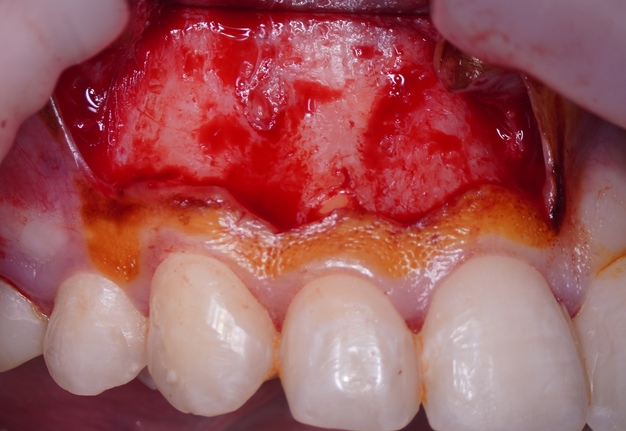

Sometimes the frenulum of the upper lip is massive and for avoid its dissection, it is permissible to perform a submarginal flap with one vertical incision located more distally. It is worth recognizing that this approach is applied to a root with medium length on which microsurgery is performed (Figs 3 and 4).

Once the apical microsurgery has been completed great care has to be taken in repositioning and suturing the elevated soft tissue. In fact, the ultimate esthetic result of the soft tissue manipulation depends on several factors such as the type of tissue, the type of incision, the choice of instruments used to incise, elevate, and retract the flap as well as careful reapproximation and a proper suture technique.

It is recommended to moisten the soft tissue with a wet gauze (sterile water or saline) before it is repositioned. The soft tissue can become dehydrated during the procedure and rehydrating it will return its natural elasticity and allows for easier reapproximation [17]. When flap shrinkage persists despite tissue rehydration, a supplementary horizontal incision may be performed at the flap base to generate a variable-thickness flap, thereby enhancing tissue adaptability and reducing contractile tension.

A good recommendation is compression of the repositioned flap with a saline-moistened piece of gauze is necessary to create a thin fibrin layer between flapped tissue and cortical bone [16].